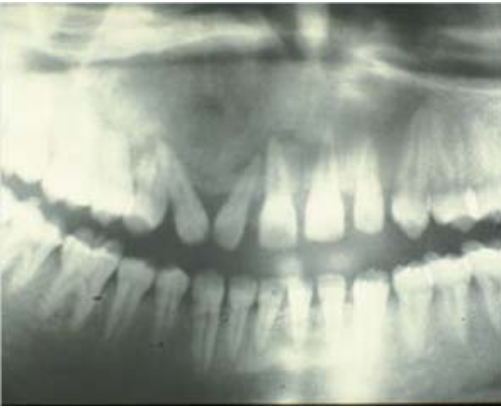

77.為何種拍攝方式所產生? (A)Water's view (B)Occlusal view (C)Submental vertex view (D)Modified Town's view

78.承上題,圖中之X光影像(箭頭所示處)最可能之X光診斷為: (A)阻生牙 (B)顎下腺結石 (C)淋巴結鈣化 (D)靜脈結石